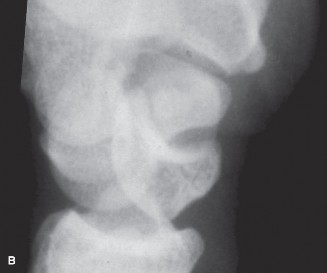

Use 1-2ICSRA to revascularize the scaphoid? CASE 3 ### A patient is brought into the emergency room following a motor vehicle accident. He complains of severe pain in his wrist. Physical examination reveals a tender and swollen wrist. X-rays (Figs. 3–5A–B) are as follows. What is your diagnosis?

Figure 3–5 A–B. (©) Sunil Thirkannad and Christine M. Kleinert.

The correct answer is (D). This x-ray reveals a perilunate injury of the wrist. It is important to be aware of the various radiological parameters that reveal disruption of carpal alignment. Literature suggests that a perilunate injury is missed as much as 25% to 40% of the times. Which radiological signs of perilunate injury can be seen on the above Figs. 3–5A–B .

The correct answer is (E). All three radiological signs are seen on this x-ray. Triangle sign refers to the shape of the lunate seen on the PA view. A normal, well located lunate looks like a tilted trapezium. A triangular-shaped lunate suggests that it is in a hyperflexed position. In the lateral view, a subluxated and volar-tilted lunate has the appearance of a “spilt teacup.” In the above x-ray, Gilula’s first and second lines are broken.